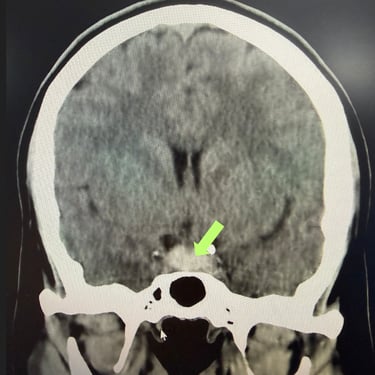

Tumor Selar Hemorrágico: Tratamiento Endoscópico Transesfenoidal.

El tumor selar hemorrágico, también conocido como apoplejía hipofisaria, es una urgencia neuroquirúrgica que puede manifestarse con cefalea intensa, alteraciones visuales y compromiso hormonal agudo. El abordaje mediante cirugía endoscópica transesfenoidal permite un acceso directo y mínimamente invasivo a la región selar, facilitando la evacuación del componente hemorrágico y la resección del tumor. Esta técnica ofrece una adecuada descompresión del quiasma óptico, preservación de estructuras neurovasculares y una recuperación más rápida. El tratamiento oportuno es clave para mejorar el pronóstico neurológico y visual del paciente.